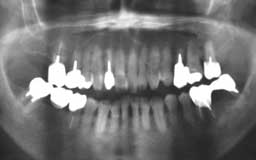

Aさん 初診時 48歳 男性

残存歯数は多いが、歯周疾患末期にさしかかる歯を含め将来が危ぶまれる状態です

Aさん 治療終了時

上下前歯部の歯周外科手術とほぼ全顎にわたる補綴処置を行い治療終了。その後メインテナ ンスを継続しましたが、数か月後から来院が途絶えてしまいました

Aさん 10年後(再来院時

10年間の間に、他院にて多少治療を行ったようですが状況が思わしくなく再び来院されまし た。その間相当数(5本)の歯を失い、残った歯もほとんど使い物にならない状態です

Aさん 初診より16年後(再治療より5年)

使えそうな歯を残してほとんどの歯を抜歯して入れ歯にしました。如何に丁寧な治療をして もメインテナンスなしでは歯を保存することは不可能です。この状態になってからはメイン テナンスの重要性を十分理解されて毎月通院されています